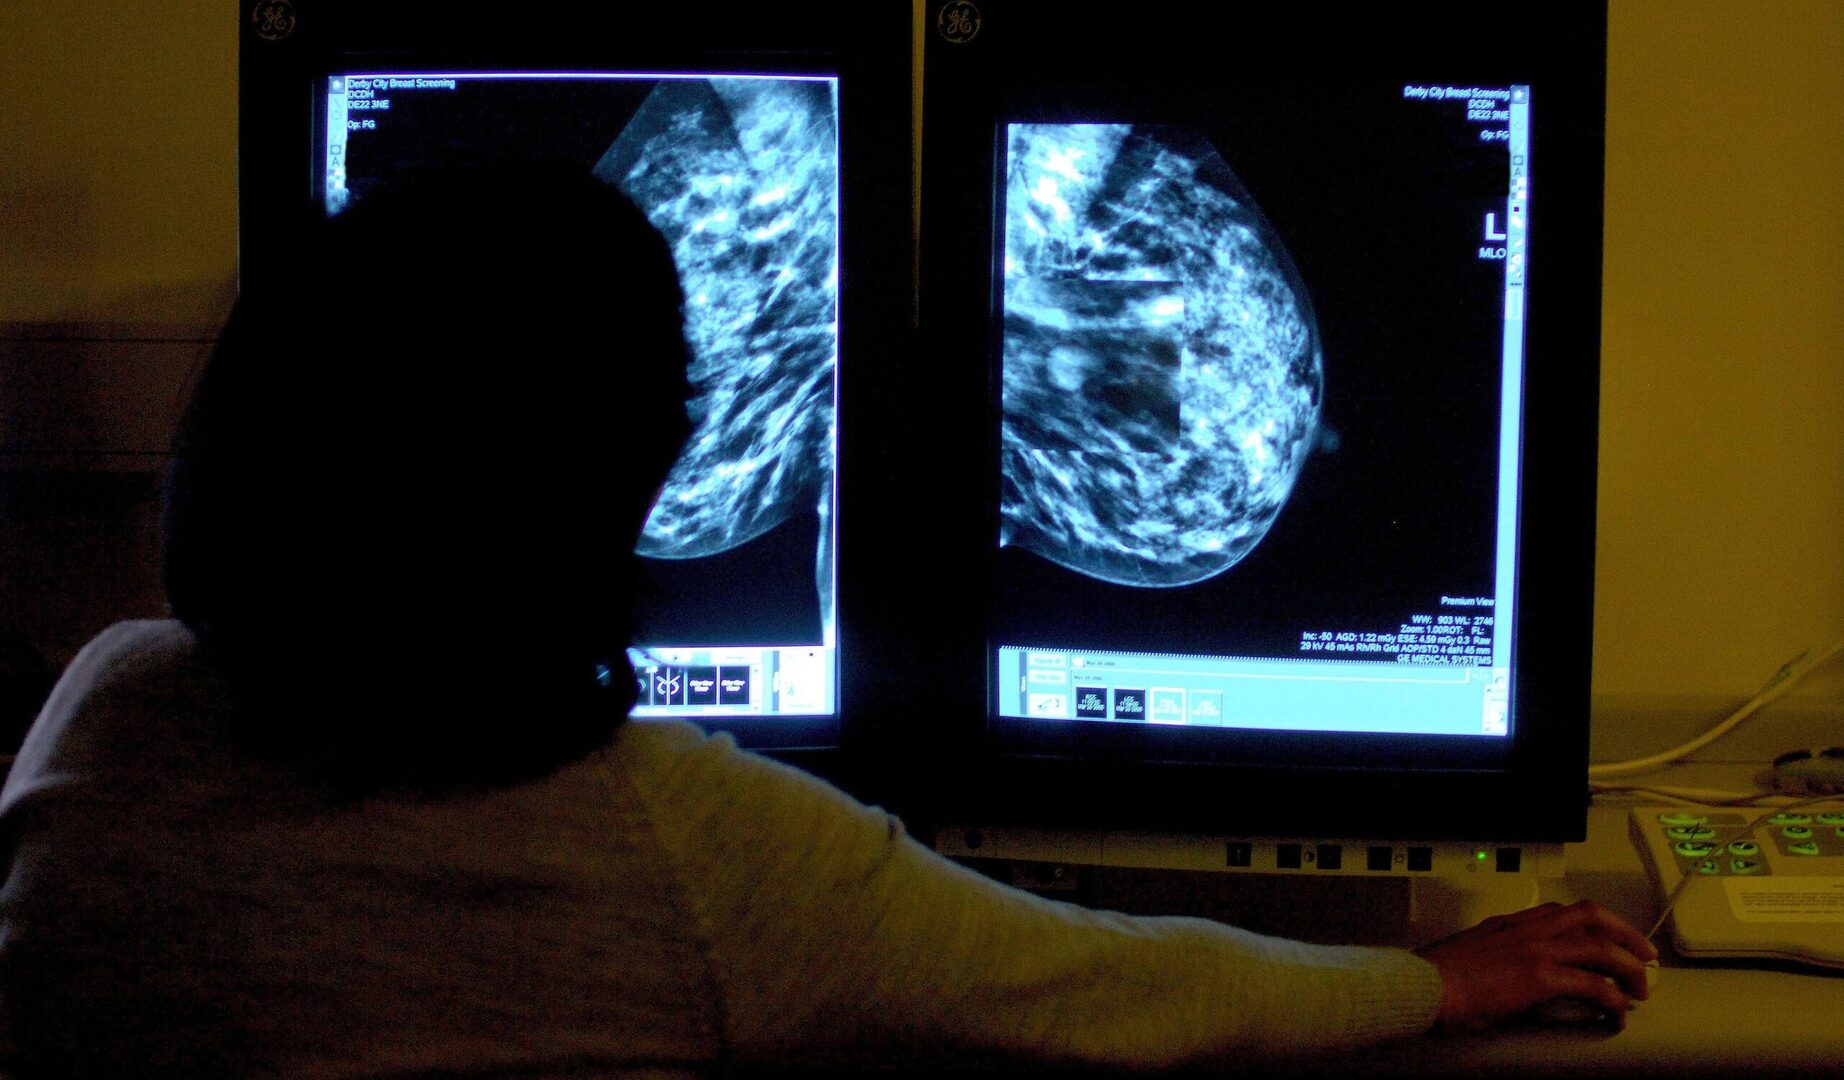

Una nueva tecnología desarrollada en la Universidad Johns Hopkins de Estados Unidos permite distinguir el líquido de las masas mamarias sólidas con una eficacia muy superior a los métodos actuales. Según publica Radiology Advances, este avance promete ahorrar a las pacientes, sobre todo a aquellas con tejido mamario denso, pruebas de seguimiento superfluas y ansiedad.

El estudio, llevado a cabo con 132 pacientes, concluyó que los radiólogos identifican correctamente las masas el 96% de las veces con este sistema, frente al 67% habitual de la ecografía tradicional.

Aunque se recomienda la mamografía a mayores de 40 años, sus resultados pueden ser inconclusos en tejidos densos. La ecografía tradicional a menudo falla ahí porque el sonido se dispersa, provocando una distorsión acústica que hace que quistes benignos parezcan tumores.